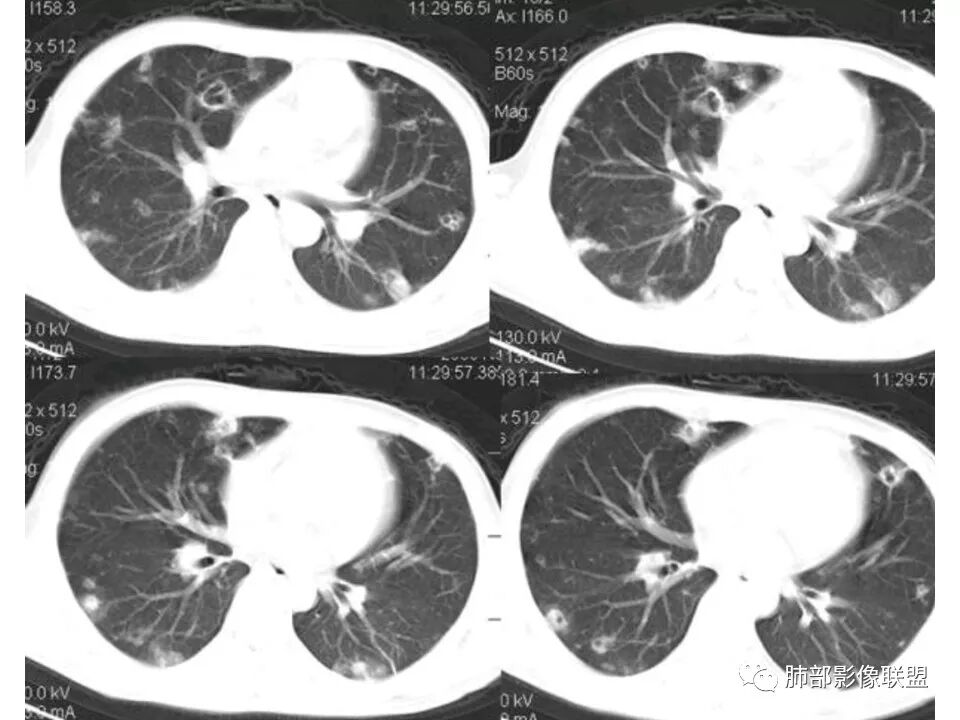

南边:青年男性,急性起病,多发结节或囊腔——胸膜下分布结节,与支气管关系不密切,支气管壁不增厚,首选血道来源,不是气道来源

南边:

血道来源的:

1、感染性:金葡菌?克雷白杆菌?曲霉菌?

2、血管炎性:血管炎?

3、肿瘤:血管肉瘤?转移瘤?

结果

(血源性)金葡菌肺炎(血培养金黄色葡萄菌)

金黄色葡萄球菌:革兰阳性菌,涂片表现为成对的短链状四联球菌或簇状。金葡菌肺炎:是由金黄色葡萄球菌引起的急性化脓性肺部感染,常发生于免疫功能受损的病人。主要分为原发性(吸入性)金葡菌肺炎和继发性(血源性)金葡菌肺炎。血源性金葡菌肺炎:常继发于金葡菌败血症及脓毒血症,由细菌栓子经血液循环至肺而引起。多表现为肺外周和基底部分布为主的多发点片状影或类圆形结节影。菌栓引起多发性肺小动脉栓塞,导致双肺多发性化脓性炎症,进而组织坏死形成多发性肺脓肿,并可累及胸膜产生脓胸或脓气胸。诊断要点:    1.金黄色葡萄球菌引起3%的社区获得性肺炎及15%的  医院获得性肺炎    2.金黄色葡萄球菌肺炎的主要危险因素是静脉输液和ICU患者。    3.常见的影像学表现:    1)单侧(60%)或双侧(40%)斑片状实变影(支气管肺炎)    2)空洞性结节(直径4~10mm)

3)CT可见小叶中心结节、树芽征及楔形变(脓毒性栓塞)

4)肺气囊形成

5 ) 脓肿形成

6 ) 胸腔积液

少见的影像学特征:弥漫性肺实变(表示支气管肺炎融合)